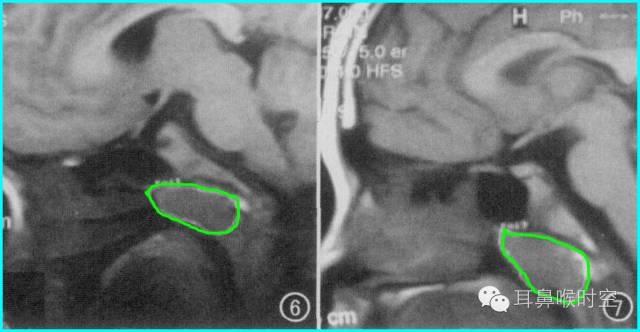

根据经典Fujioka 等 X 线平片测量法原理:

A/ N 比:测量腺样体最大厚度与自硬腭上缘到颅底蝶枕骨的软骨结合部的距离之比

PAS:后气道间隙(pharyngealairway space , PAS)的宽度(软腭表面与腺样体表面之间有效气道宽度)。

采用SE 序列矢状面T1WI

选择正中矢状面,分别测量两条径线(图1、2)

N 线:即从蝶骨体2枕骨斜坡的软骨结合部后缘(O点)至硬腭与软腭上缘交界处的连线N

A 线:过O点沿枕骨斜坡下缘作延长线L,取腺样体下缘最凸点作L线的垂直线。

A/N比:分别测A、N值,计算A/N 比

正常组镰刀形(图4)、刀鞘形(图5)为主

镰刀形、刀鞘形,腺样体厚度较薄,下缘凹陷或平直,但均不下凸

肥大组子弹形(图6)、山丘形(图7)为主

肥大组:子弹形、山丘形,腺样体饱滿、下凸,象山丘样突出。在冠状面上腺样体表现为“马鞍形”和“倒置梯形”。

解剖结构:在MRSET1WI 鼻咽部正中矢状面图像上,由于采取薄层断面成像

可以直观显示腺样体本身

清晰显示蝶骨体与枕骨斜坡之间的软骨接合部、鼻后孔间隙、鼻甲、硬腭与软腭上缘的交界面、软腭、会厌软骨等结构

易于测量:非常容易画出A 线及N 线,及测量PAS,了解鼻后孔间隙、鼻甲大小、软腭厚度及后突程度